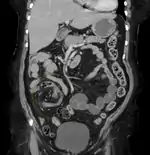

Coronal CT of the abdomen, demonstrating a volvulus as indicated by twisting of the bowel stock

A volvulus is when a loop of intestine twists around itself and the mesentery that supports it, resulting in a bowel obstruction.[1] Symptoms include abdominal pain, abdominal bloating, vomiting, constipation, and bloody stool.[1][2] Onset of symptoms may be rapid or more gradual.[2] The mesentery may become so tightly twisted that blood flow to part of the intestine is cut off, resulting in ischemic bowel.[1] In this situation there may be fever or significant pain when the abdomen is touched.[2]

Risk factors include a birth defect known as intestinal malrotation, an enlarged colon, Hirschsprung disease, pregnancy, and abdominal adhesions.[1] Long term constipation and a high fiber diet may also increase the risk.[3] The most commonly affected part of the intestines in adults is the sigmoid colon with the cecum being second most affected.[1] In children the small intestine is more often involved.[5] The stomach can also be affected.[6] Diagnosis is typically with medical imaging such as plain X-rays, a GI series, or CT scan.[1]